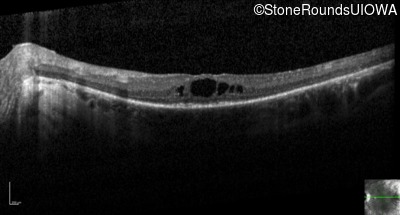

Optical Coherence Tomography - Left - 20/70 +1

Exemplar / OCT Stack